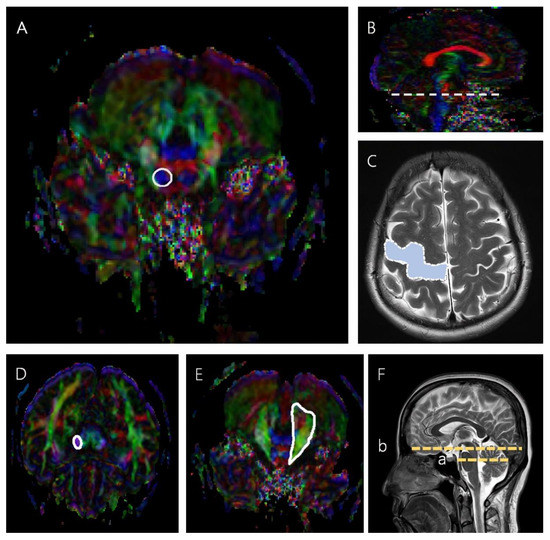

2.3. Diffusion Tensor Tractography